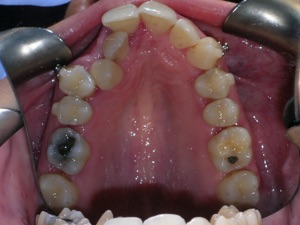

This case was of a young lady who desperately wanted Invisalign, but had been told it was not possible. There was not one, but two teeth that had come in toward the roof of the mouth.

Here are some progress photos.